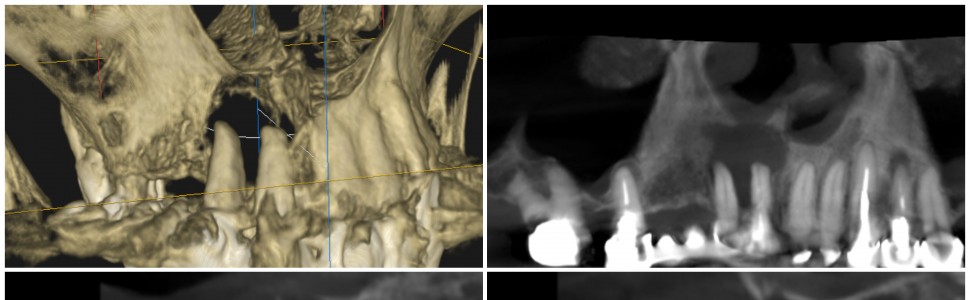

Artykuł omawia przypadek leczenia endodontycznego zębów 12 i 11 z rozległą zmianą okołowierzchołkową, która obejmowała swym zasięgiem blaszkę wargową, podniebienną wyrostka zębodołowego i podstawę kostną nosa. Skuteczne leczenie spowodowało całkowitą remisję zmiany, co wyeliminowało konieczność interwencji chirurgicznej. Autor podsumowuje, że leczenie endodontyczne nadal stanowi podstawowe narzędzie w zachowaniu naturalnych zębów, nawet w przypadkach z rozległymi zmianami kostnymi. Poprawnie leczone i zarządzane zęby poddane leczeniu kanałowemu mają przewagę nad implantami stomatologicznymi. Przedstawiony przypadek pomaga określić ograniczenia i czynniki uwzględniane przy stosowaniu tej metody leczenia, podkreślając znaczenie stabilizacji zęba i odpowiedniego wyboru pacjentów.

The article discusses a case of endodontic treatment of teeth 12 and 11 with an extensive periapical lesion that involved the buccal and palatal plates of the maxillary tuberosity and the nasal floor. Successful treatment resulted in complete remission of the lesion, eliminating the need for surgical intervention. The author concludes that endodontic treatment remains a fundamental tool in preserving natural teeth, even in cases with extensive bone changes. Properly treated and managed root canal-treated teeth have an advantage over dental implants. The presented case helps identify limitations and factors to consider when using this treatment method, emphasizing the importance of tooth stabilization and appropriate patient selection.